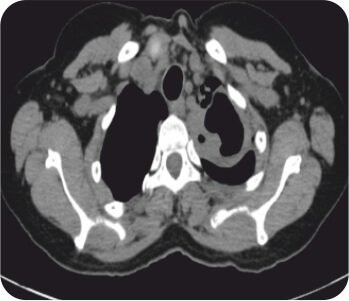

সিটি বুক বাম উপরের লোবে গহ্বরের ইঙ্গিত দেয়। এফওবি বাম উপরের লোব ব্রঙ্কাস থেকে পুস নির্গত হওয়ার পরামর্শ দিয়েছিল এবং বাম উপরের লোব ব্রঙ্কাসে একটি জমাট ভরের সাথে অনুগত। পরবর্তী ব্রঙ্কোঅ্যালভিওলার ল্যাভেজ প্রধানত নিউট্রোফিলিক ছিল। পাইজেনিক, ছত্রাক, যক্ষ্মা এবং নোকার্ডিয়ার জন্য দাগ এবং সংস্কৃতি নেতিবাচক ছিল। সাইটোলজি ম্যালিগন্যান্সির জন্য নেতিবাচক ছিল। ইনভেসিভ মিউকোরমাইকোসিসের একটি নির্ণয় করা হয়েছিল।

সিটি বুক - বাম উপরের লোবে গহ্বর